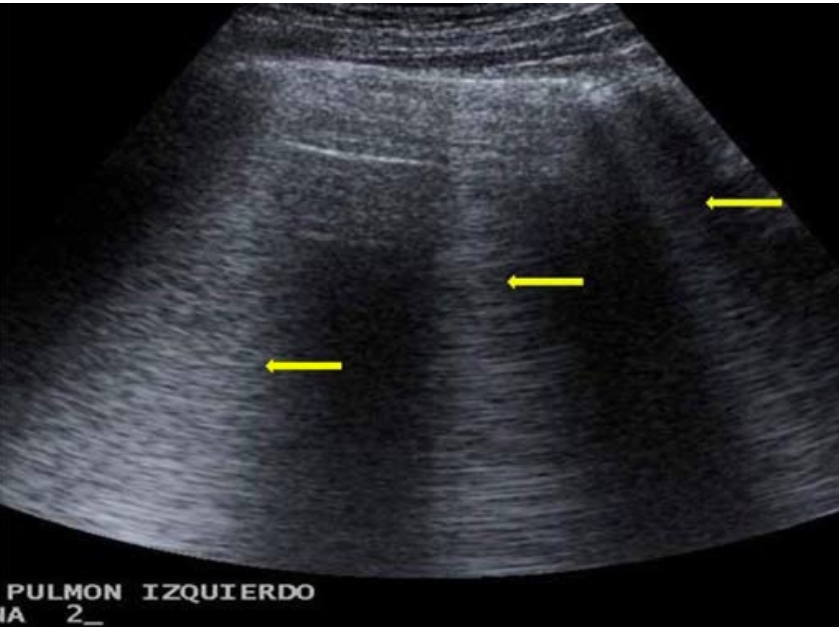

B 线

垂直于胸膜线并指向肺实质的三角形伪像,其纵深可长达 17 cm,并可与胸膜同步滑动(图 1)。

若出现 3 条以上的 B 线且彼此间距< 7 mm 时,表示间质性水肿

若间距<3 mm 时,称为彗尾征(图 2),系由间质性水肿所引起的混响伪像。